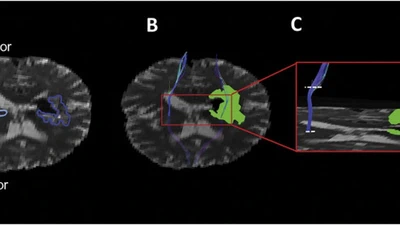

Peri-Hematoma Corticospinal Tract Integrity in Intracerebral Hemorrhage Patients: A Diffusion-Tensor Imaging Study.

BACKGROUND: The impact of perihematoma edema in Intracerebral Hemorrhage (ICH) on white matter integrity is uncertain. Fractional Anisotropy (FA), as measured with Diffusion Tensor …